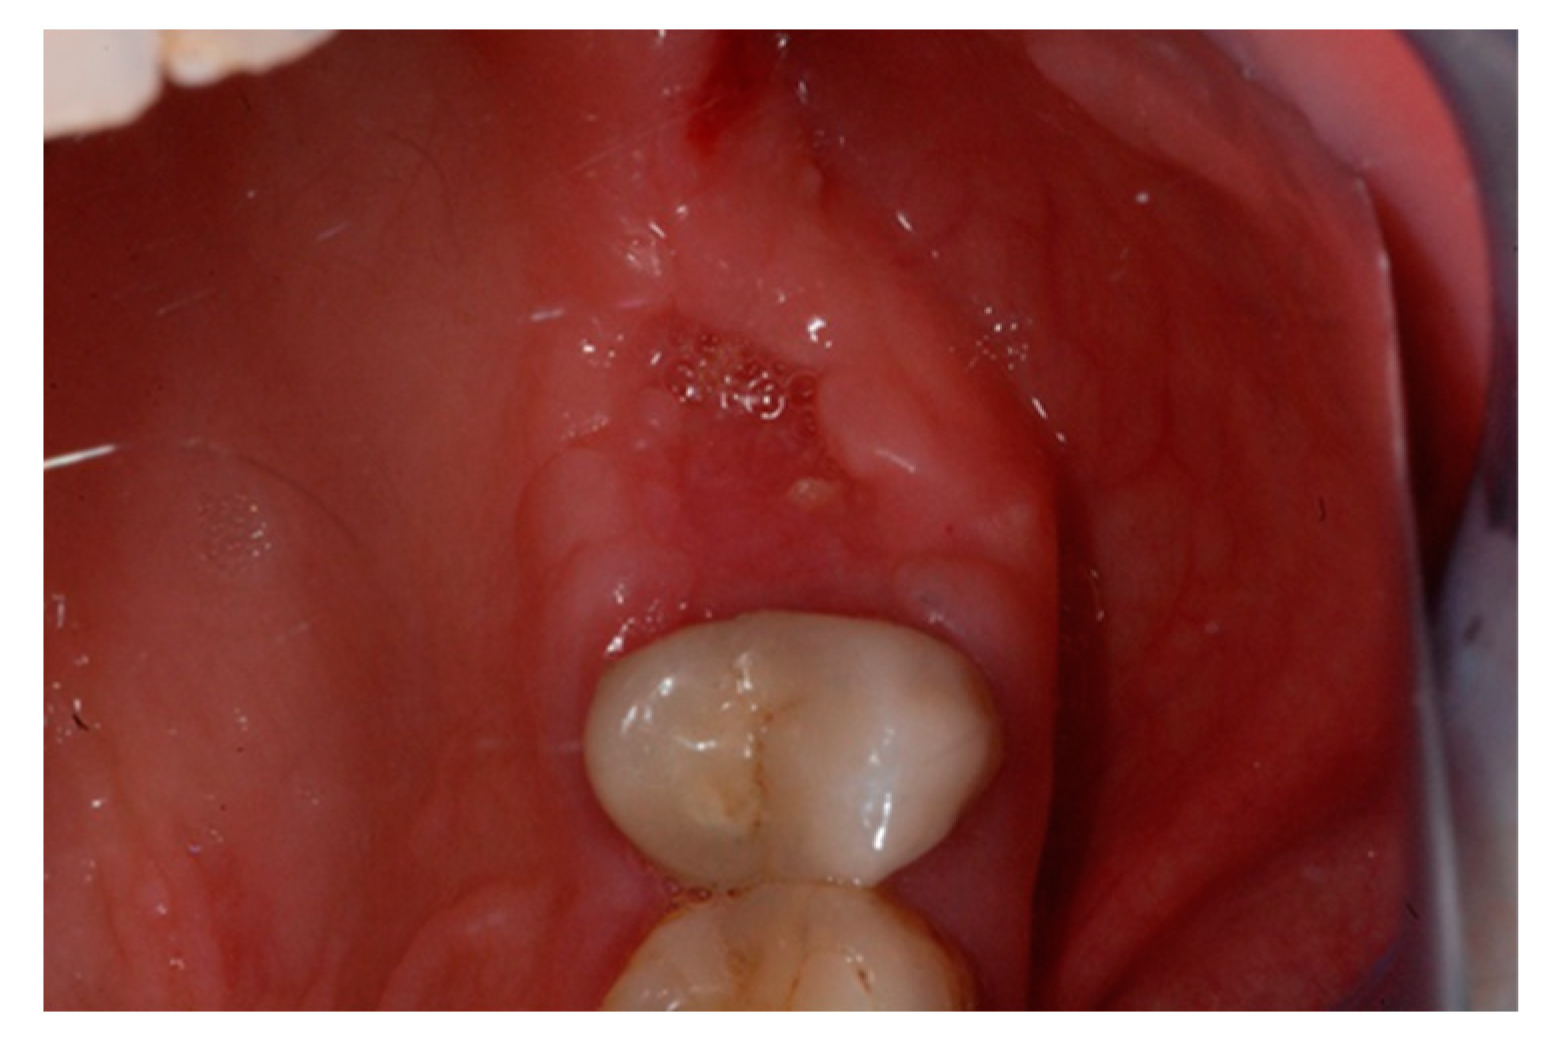

2. Case Report